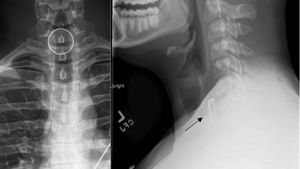

Ngilu! Penampakan Tutup Botol Nyangkut di Tenggorokan, Tak Sengaja Tertelan